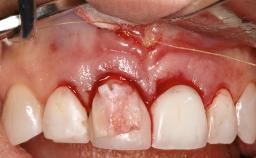

Paolo Casentini demonstrates that peri-implantitis can be successfully treated even at an advanced stage. He discusses a case in which the existing implants and prostheses were both retained while regenerating the defect and creating a band of keratinized tissue. A 69-year-old female patient was referred by her general dentist for evaluation of a recurrent infection at previously placed and restored implants in the posterior left mandible. The patient’s chief complaint was recurrent swelling and pain in the molar region of the left posterior mandible with discomfort during brushing in the same area. The patient reported receiving two implants (36 and 37) nine years earlier.